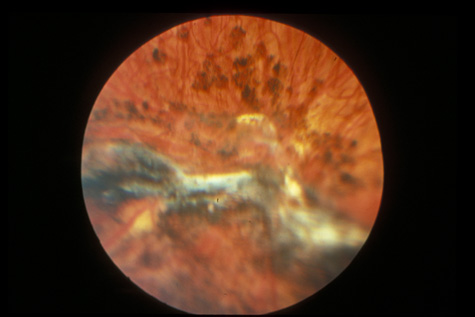

rupture. Am J Ophthalmol 79:977, 1975 89. Smith RE, Kelley JS, Harbin TS: Late macular complications of choroidal rupture. Am J Ophthalmol 77:650, 1974 90. Rogers AH, Duker JS, Nichols N: Photodynamic therapy of idiopathic and inflammatory choroidal neovascularization

in young adults. Ophthalmology 110:1315, 2003 91. Sickenberg M, Schmidt-Erfurth U, Miller J: A preliminary study of photodynamic therapy using verteporfin for choroidal

neovascularization in pathologic myopia, ocular histoplasmosis syndrome, angioid

streaks, and idiopathic causes. Arch Ophthalmol 117:327, 2000 92. Kylstra JA, Lamkin JC, Runyan DK: Clinical predictors of scleral rupture after blunt ocular trauma. Am J Ophthalmol 115:530, 1993 93. Joondeph BC, Young TL, Saran BR: Multiple scleral ruptures after blunt ocular trauma. Am J Ophthalmol 108:744, 1989 94. Levin LA, Beck RW, Joseph MP, et al: The treatement of traumatic optic neuropathy: The International Optic Nerve